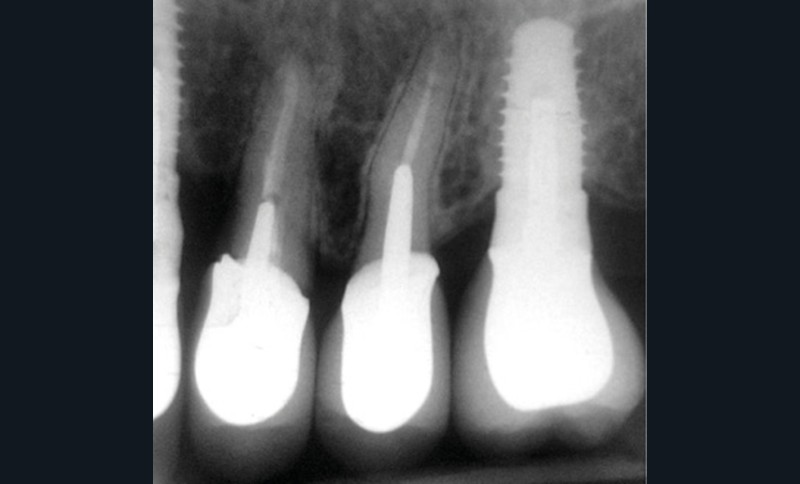

Une patiente de 64 ans, en bonne santé générale, suivie en maintenance parodontale depuis sept ans (parodontite 3B), est vue en juin 2014 pour l’extraction de sa 24 en raison d’infections endodontiques récurrentes. Le plan de traitement prévoit la pose extemporanée d’un implant et sa restauration prothétique quatre mois plus tard. La 25 est une dent couronnée et 23 et 26 sont des restaurations implantaires (fig. 1a à c). La dent antagoniste 35 est une restauration implantaire.

La radiographie péri-apicale au long cône confirme, sur la 25, un élargissement desmodontal, notamment en distal, des niveaux osseux mésio-distaux réduits par rapport aux clichés de contrôle précédents (les radiographies sont réalisées avec une technique parallèle avec des angulateurs de Rinn non personnalisés), un apex radiculaire normal et des niveaux osseux stables sur les implants adjacents (fig. 5). Le cisaillement systématique du fil dentaire lors de son passage confirme des points de contact très étroits entre 24, 25 et 26.